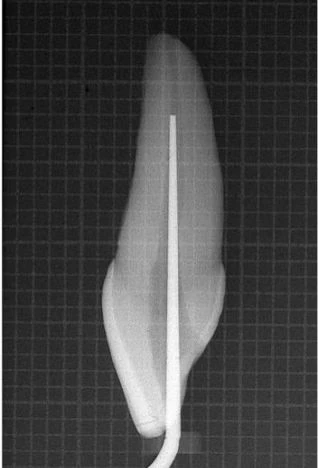

Những vùng cong này cần được loại trừ trước bằng phương pháp “kháng độ cong” của Abou-Rass, Frank, và Glick như đã nói trên. Nếu xoang tủy giúp dụng cụ sửa soạn ống tủy có thể vào thẳng đến 1/3 chóp thì vật liệu và dụng cụ trám bít cũng vào được (hình 11.9).

Hình 11.9. Xoang tủy được làm đúng cho phép đi thẳng vào 1/3 chóp chân răng, thậm chí cả dụng cụ trám ống tủy cũng vào được